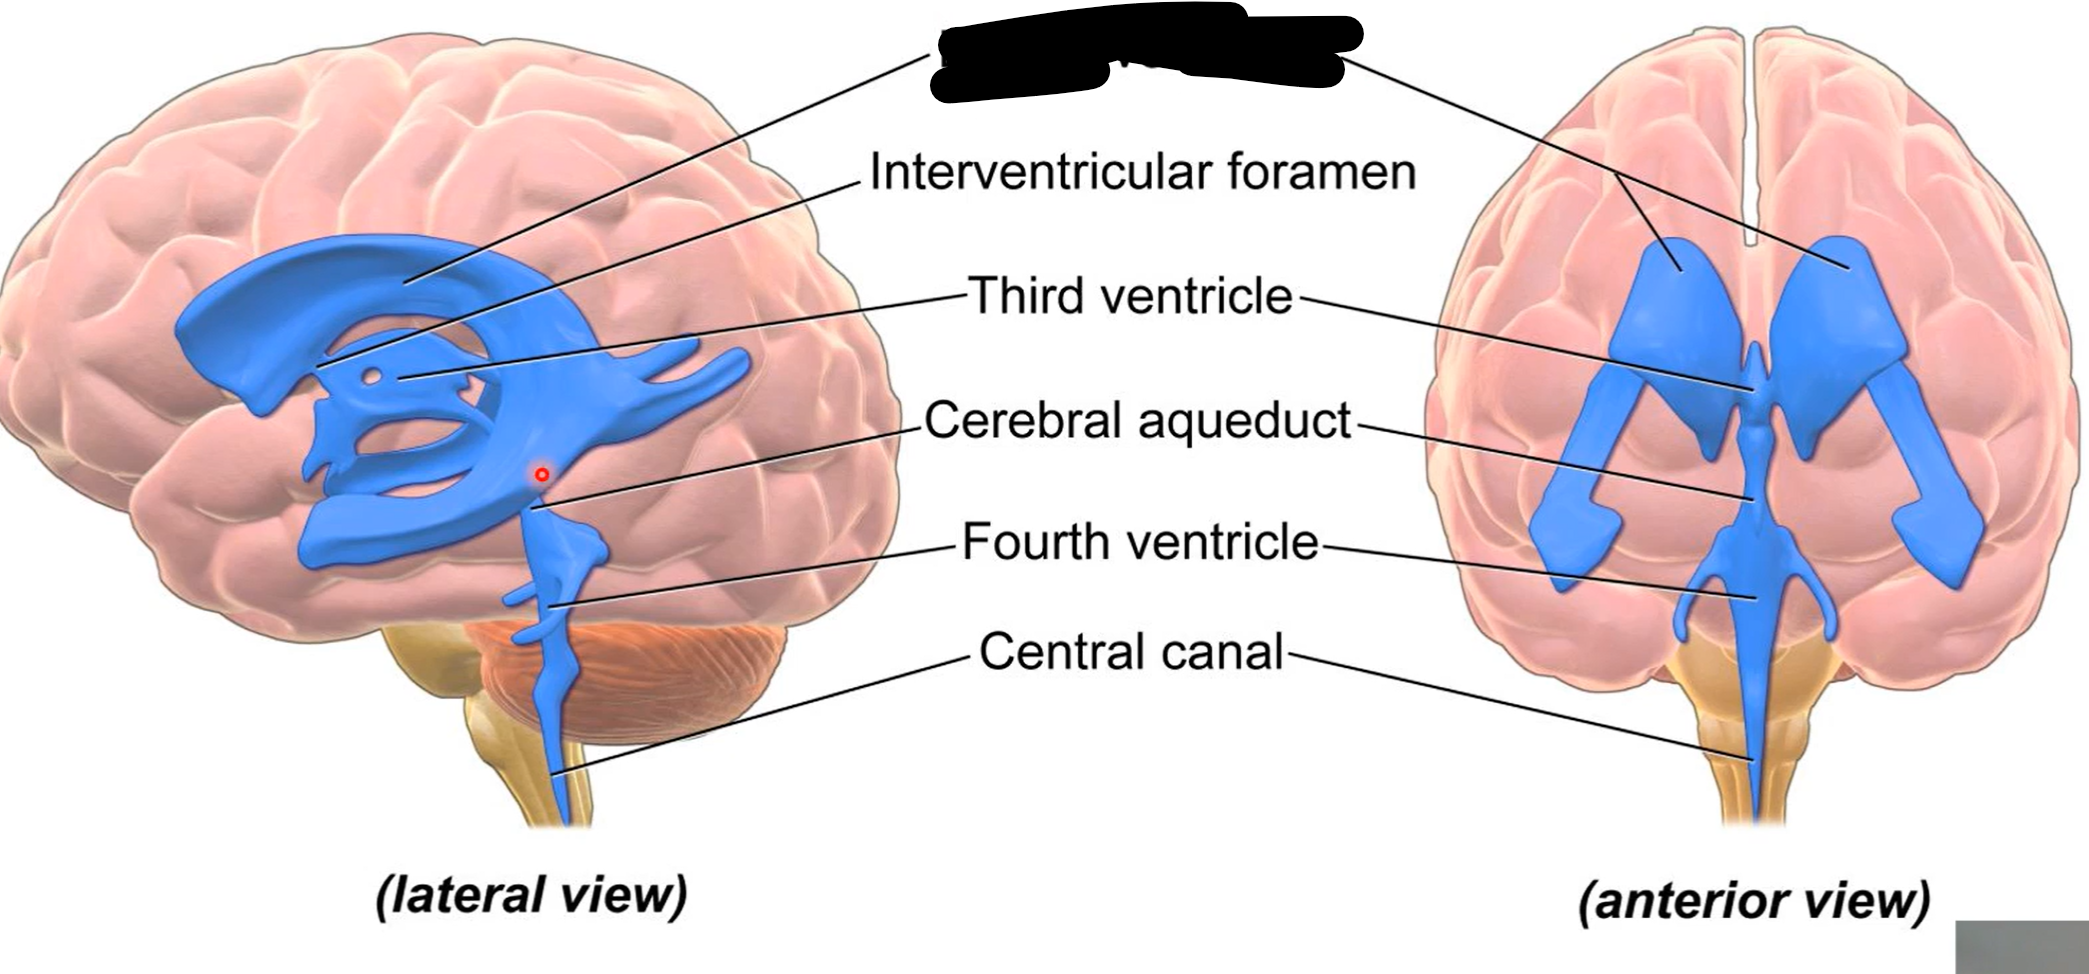

What do brain ventricles contain?

CSF

What makes CSF?

Choroid plexus

Where does CSF go from ventricles?

Subarachnoid space to enter circulation via arachnoid granulations

Choroid plexus

What carries CSF from 4th ventricle to subarachnoid space?

Median and lateral apertures

Arachnoid granulations

Lateral ventricles

Interventricular foramen

Third ventricle

Cerebral aqueduct

Fourth ventricle

Central canal